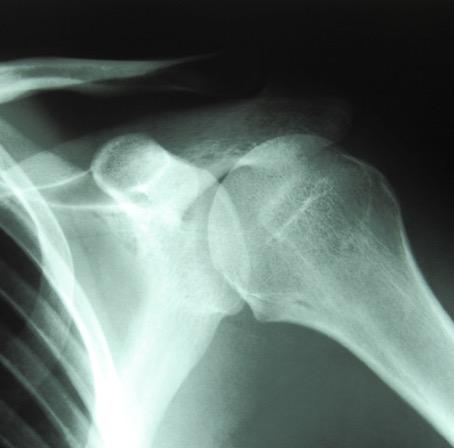

"Rotator Cuff Tear: A Common but Confusing Cause of Shoulder Pain,” on Tuesday, Nov. 17, at 7 p.m., in Classroom 1 on the second floor of the Wright State Physicians Health Center (725 University Blvd.) on the campus of Wright State University. The session is free and open to the public.

He will speak about how rotator cuff tears are one of the most common causes of shoulder pain in adults; different types of rotator cuff tears; and nonsurgical options for rotator cuff tears.